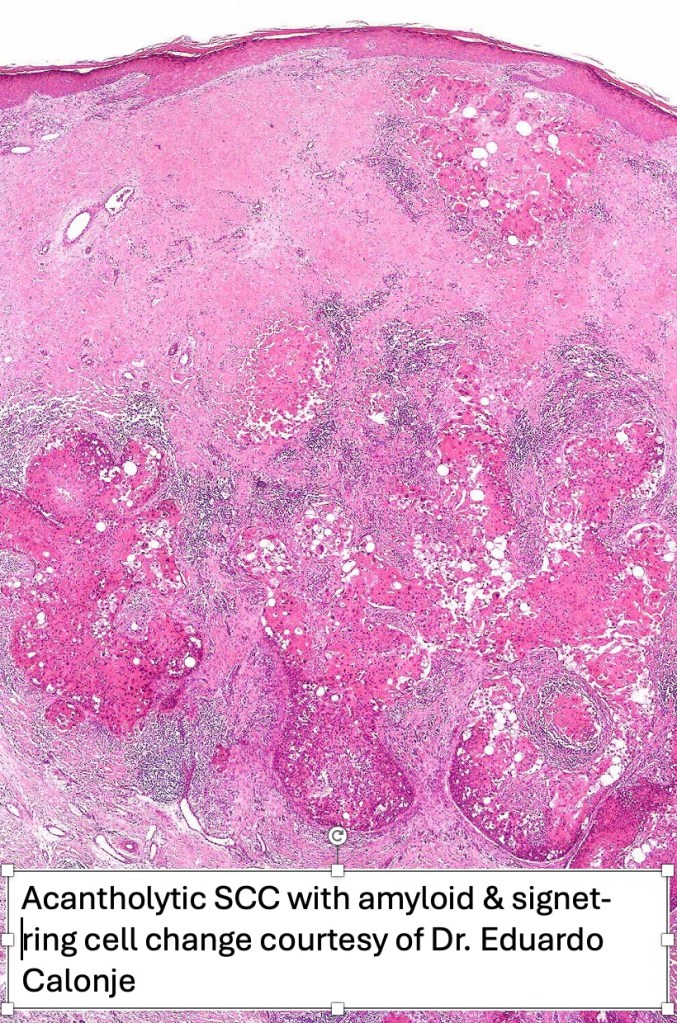

•Acantholysis gives rise to a pseudoglandular appearance

•Often well differentiated

•Amyloid may be present

•Exceptional associated signet-ring cell change (signet ring cell squamous carcinoma)